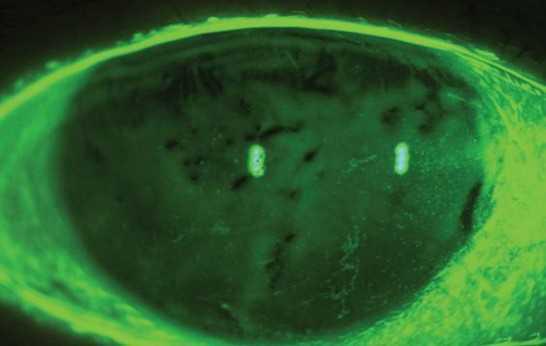

Hialuronato Sódico 0.15% (Hyabak) fue la única gota categorizada como hipoosmolar en comparación con las lágrimas humanas (osmolaridad inferior a 275 mOsm/L). Otras gotas se categorizan como isoosmolares (osmolaridad similar a las lágrimas humanas). Foto: Luis Rojas, OD.